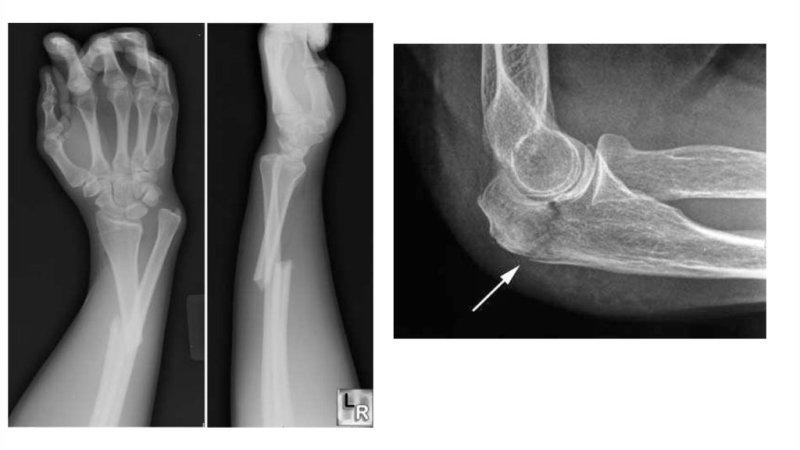

Диагностика перелома предплечья

Специалист сможет установить диагноз после клинического обследования, которое включает в себя пальпацию поврежденной области, внешний осмотр и общение с пациентом. Тем не менее, для окончательной и точной диагностики требуется проведение рентгенологического исследования.

Кроме того, важно определить наличие переломных вывихов, так как игнорирование повреждений капсулы локтевого сустава может привести к серьезным последствиям.